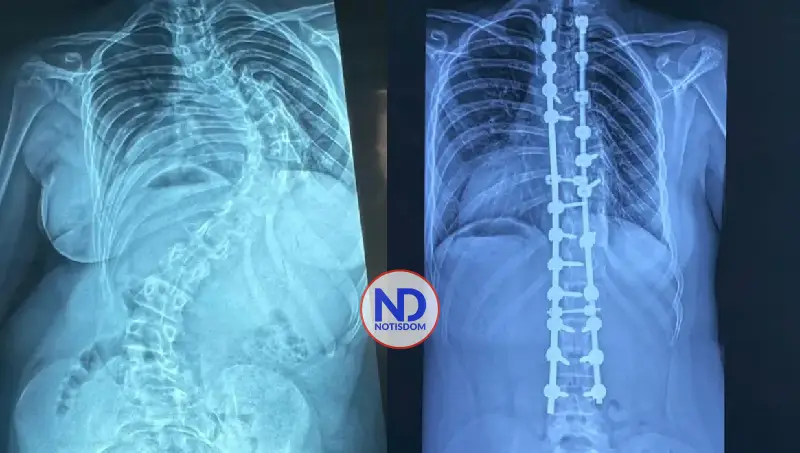

SANTO DOMINGO.– En los últimos cuatro años se han realizado 350 cirugías de deformidades de la columna vertebral pediátrica en la República Dominicana, distribuidas entre el Hospital Infantil Robert Reid Cabral y la Sociedad Dominicana de Rehabilitación, bajo la coordinación del doctor Carlos Rodríguez Estévez.

Ambas instituciones han consolidado equipos multidisciplinarios especializados, lo que ha permitido que niños y adolescentes con escoliosis y otras deformidades espinales reciban tratamiento oportuno en el país, mejorando significativamente su calidad de vida.

En la unidad de escoliosis del Hospital Infantil Robert Reid Cabral se han realizado más de 250 cirugías de esta condición, una enfermedad que afecta a cientos de niños y adolescentes en el país.

El doctor Carlos Rodríguez explicó que, gracias al personal humano capacitado y a la tecnología disponible en ese centro de salud, pacientes de escasos recursos pueden optar por este procedimiento quirúrgico, cuyo costo ronda el millón de pesos y que no puede realizarse en cualquier institución.

La escoliosis es una desviación de la columna vertebral mayor de 15 grados. El especialista detalló que la forma más frecuente es la idiopática del adolescente.

«Es una patología que básicamente va a mermar la calidad de vida de los pacientes, porque esas desviaciones que continúan progresando durante el crecimiento pueden comprimir órganos internos como el corazón y los pulmones», explicó.

Sobre los resultados, destacó que muchos pacientes intervenidos hoy llevan una vida normal.

«Después de una cirugía como esta pueden hacer su vida prácticamente normal, en igualdad de condiciones que cualquier otro niño».